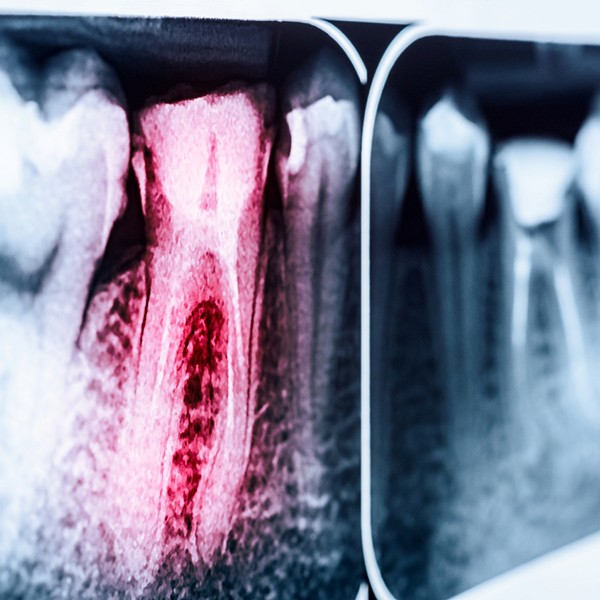

Root canal treatment was designed to treat teeth with severe decay or damage, or teeth with infected pulp. Please be aware that even if you aren’t experiencing any painful symptoms, your tooth could still be infected and pose a danger to other nearby teeth. Worse yet, infections can spread beyond just the teeth and throughout the body, causing serious illness.

There are many reasons you may need a root canal, such as a broken tooth or untreated cavity which could allow harmful oral bacteria to infect your sensitive tooth pulp.

Your root canal treatment will always begin with Dr. Hegazi administering local anesthesia to the area needing treatment, so it is completely numb before any work begins. Next, Dr. Hegazi will use small, special instruments to remove the infected pulp that is responsible for your toothache. Once it is cleared away, the tooth will be filled with a synthetic material called gutta percha, which rebuilds the structure and shape of the tooth. A temporary crown will then be placed on the tooth until your permanent restoration arrives, usually in about two weeks. Once your permanent crown arrives, you will be scheduled to return to Admired Smiles, where your temporary crown will be removed and your permanent crown will be cemented in place.